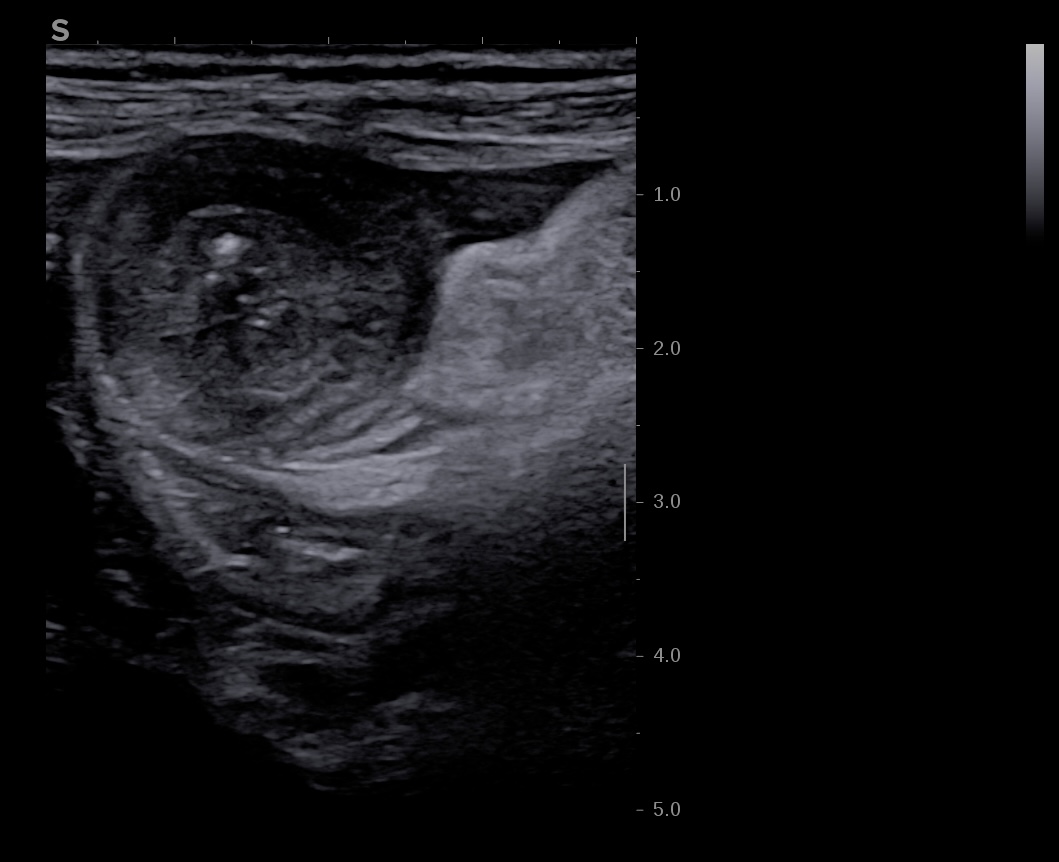

- IMportante et localisée dans la diverticulite, ou importante et diffuse en cas de complication (fistule et abcès)

- Plus l'inflammation atteint la séreuse, plus la graisse environnante devient infiltrée

- plus importante en cas d'inflammation transmurale, type Crohn ou colite ischemique.